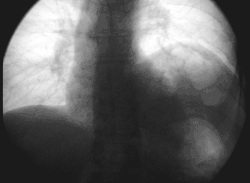

Left phrenic nerve palsy (right image side) in fluoroscopy: forced inspiration with the closed mouth leads to paradox elevation of the paralytic left diaphragm while the healthy right side moves down.

Pain arising from structures supplied by the phrenic nerve is often "referred" to other somatic regions served by spinal nerves C3-C5. For example, a subphrenic abscess beneath the right diaphragm might cause a patient to feel pain in the right shoulder.